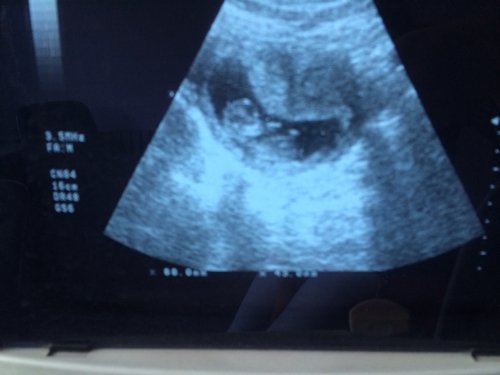

70天做B超的图片,是男孩还是女孩呢?大家都帮我看看,好人有好报!

孕四月胎儿性别形成!孕涉耀妈妈还要耐心等待!安心养胎!富脂只有这样宝宝化键炼出生后才会更加快乐健康!祝幸福~

对不起别说70天了就是七个月你也看不出来,因为一是你孩子生殖器没发育出来另外即使发育出来超声也不会显示生殖器的